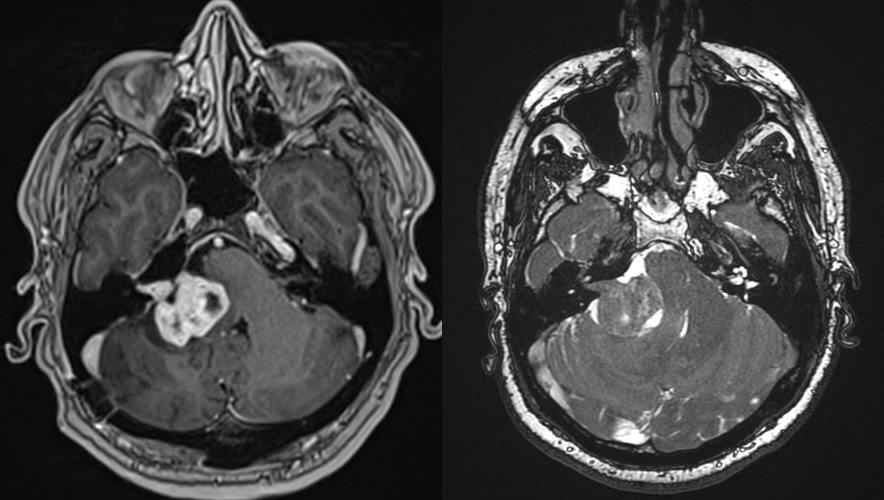

RMN cerebral cu substanță de contrast – Este cea mai precisă metodă pentru diagnostic. RMN-ul evidențiază tumora și arată dimensiunea și localizarea exactă precum și eventualele complicații (hidrocefalie). Pentru tumorile de mici dimensiuni există o secvență specială care vizualizează mai bine nervii cranieni (în funcție de tipul de aparat se poate numi CISS, TRUFI sau FIESTA).

Pe RMN, schwanomul vestibular apare ca o masă nodulară cu priză de contrast, bine delimitată, localizată în spațiul dintre stânca temporală și cerebel, cu origine în porul acustic intern.

Diagnosticul diferențial se face cu alte tumori care se pot dezvolta în această locație, în special meningioamele. Mai rar poate fi vorba și de un chist epidermoid, o determinare secundară sau o tumoră de glomus jugular. O situație aparte, deși rară, o constituie scwanoamele dezvoltate dina lți nervi cranieni – cel mai adesea nervul trigemen.